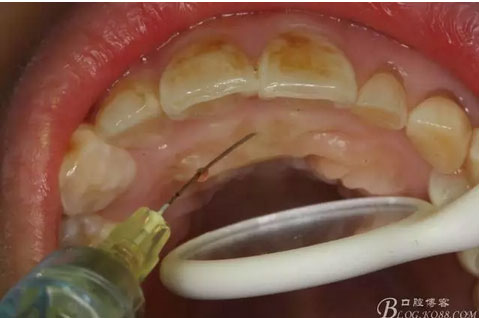

圖4.唇側局部浸潤麻醉。注意要多點浸潤麻醉。

圖5.腭側局部多點浸潤麻醉。粘膜發(fā)白即可。